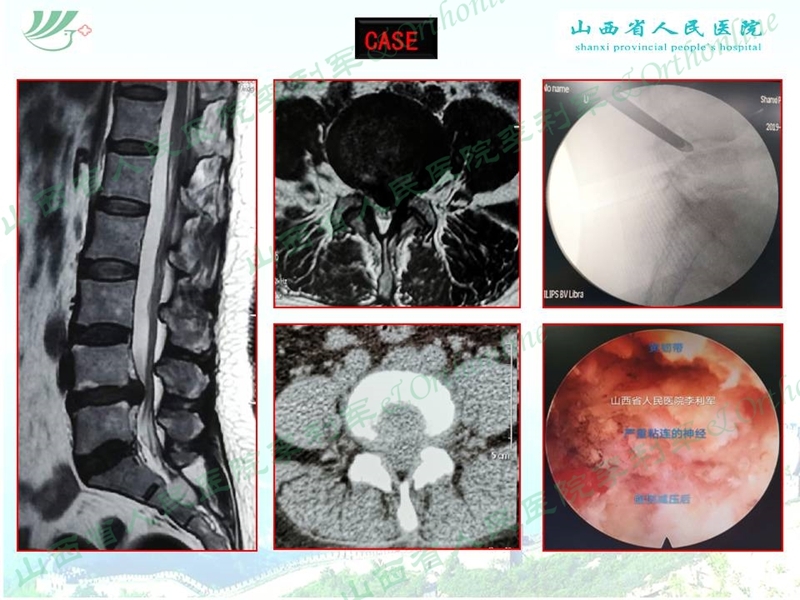

椎间孔镜技术治疗腰椎间盘突出症目前已经是一项比较成熟的技术,对于普通的腰椎间盘突出症的治疗来讲,利用常规的穿刺、置管及镜下操作都可以顺利完成手术,但我们在临床上会遇到一些不典型的、特殊类型的腰椎间盘突出,单纯按照常规技巧去做,可能会遇到一些棘手的问题,导致手术难以顺利完成,甚至出现某些并发症。

山西省人民医院李利军医生根据自己临床遇到的部分病例,归纳常见的特殊腰椎间盘突出为:高度游离间盘突出,伴有钙化的间盘突出,巨大间盘突出,复发间盘,极外侧间盘突出,易误诊为肿瘤的间盘突出,伴有神经变异的间盘突出等;并根据自己的临床体会对以上特殊类型间盘突出的孔镜治疗作了一些技术总结,以期达到抛砖引玉的作用,并等到大家的批评和指导。